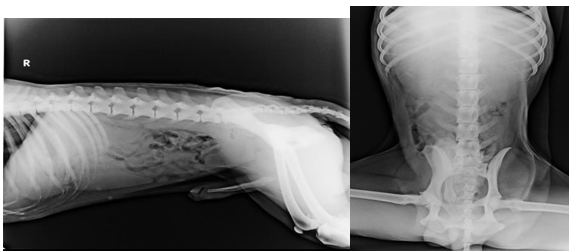

Two abdominal survey radiographs of dogs i.e. ventro-dorsal and right lateral radiograph were taken before administration of contrast agents to evaluate the suitability of contrast radiography for determination of the size, shape and position of the urinary organs. Faint impression of left kidney was visible in right lateral radiograph and both kidneys were clearly visible in ventro-dorsal radiograph in both the groups (Figure 1). The accumulation of radiolucent gas was noted in the different parts of gastrointestinal tract in the survey radiograph in both the groups. Survey radiograph provided very little details of the urinary organs or tract as a result of reduced subject contrast. Ventro-dorsal view provided better detail than right lateral view for visualization of kidneys and ureters without any superimposition of images. After administration of contrast agents, urogram was obtained immediately (0 minute) and then at 5, 15 and 30 minutes interval as reported by Velesova and Ledecky.5 The image quality of non-ionic low osmolar (iohexol) and ionic high osmolar (sodium and meglumine diatrizoate) contrast agents for intravenous urography in dogs at different time intervals are shown in Table-1, Figure 2 and Figure 3.

Figure 1 Survey radiographic image of urinary system in a clinically healthy dog.